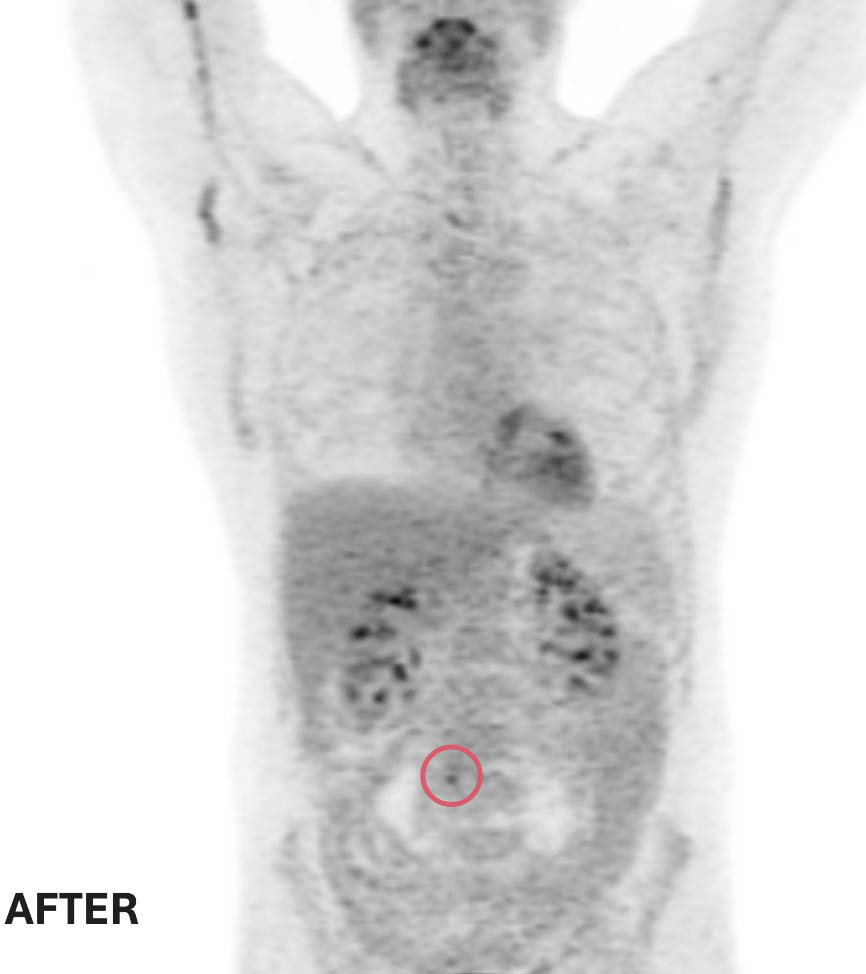

Ted’s response to treatment was extraordinary. Follow-up scans showed the two smaller masses had completely disappeared, and the large abdominal tumour had shrunk to a tiny spot, smaller than a pea. Given the aggressive nature of double-hit lymphoma, Ted’s care team recommended a short course of radiation therapy to eliminate any remaining cancer cells — a precautionary measure to reduce the chance of recurrence.

Before and after treatment scans: Two of Ted’s three tumors completely disappeared. The remaining tumor was reduced to smaller than a pea — a remarkable response to treatment at The Ottawa Hospital.